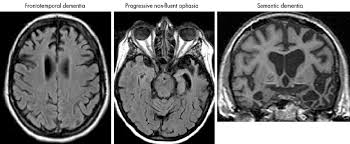

Neuroimaging In Dementia An Update For The General Clinician Progress In Neurology And Psychiatryprogress In Neurology And Psychiatry

Neuroimaging In Dementia An Update For The General Clinician Progress In Neurology And Psychiatryprogress In Neurology And Psychiatry from wileymicrositebuilder.com

Lewy, the scientist who discovered them. Loss of substantia nigra hyperintensity on 7 tesla mri of parkinson's disease, multiple system atrophy, and progressive supranuclear palsy. Besides nuclear imaging methods, the clinical utility of structural neuroimaging with magnetic resonance imaging (mri) for differential comparison between dementia with lewy bodies and alzheimer's disease. You also might see things that aren't there, called hallucinations. Lbd is a term that covers two conditions that have similar. Protein deposits, called lewy bodies, develop in nerve cells in the brain regions involved in thinking, memory and movement (motor control). Certain nuclear scans of the brain, including positron emission. How is lewy body dementia (ldb) diagnosed? Dr michael firbank discusses his study using functional mri in lewy body dementia and alzheimer's disease at the newcastle university institute. Focal atrophy in dementia with lewy bodies on mri: Memory loss is not always an early symptom. Lewy body dementia (lbd) is a type of progressive dementia. Many people also experience changes in alertness including daytime sleepiness, confusion or staring spells.

Protein deposits, called lewy bodies, develop in nerve cells in the brain regions involved in thinking, memory and movement (motor control). It's rare in people under 65. Also, there is a helpline for support provided by dementia. Dementia with lewy bodies (dlb), also known as lewy body disease, is a neurodegenerative disease (a synucleinopathy to be specific) related to parkinson disease. Dementia with lewy bodies appears to be the second most common form of dementia, accounting for about one in five cases. Further research is needed to clarify the relationships among them. Some scans (ct and mri scans) look at how the different parts of the brain fit together, rather than how the parts work together. The deposits are called lewy bodies and are named after friedrich h. Dementia is the name for problems with mental abilities caused by gradual changes and damage in the brain. Lewy body dementia, also known as dementia with lewy bodies, is the second most common type of progressive dementia after alzheimer's disease dementia. Certain nuclear scans of the brain, including positron emission. This may include a magnetic resonance imaging (mri) or computed tomography (ct) scan of the brain. After alzheimer disease (ad), dementia with lewy bodies (dlb) is one of the most common types of degenerative dementia.